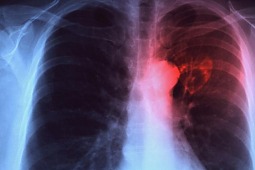

Czy grozi nam epidemia gruźlicy?

W Polsce spada liczba zachorowań na gruźlicę, a jednak nasz kraj znajduje się w strefie zagrożenia zwiększoną zachorowalnością - wynika z informacji ministerstwa zdrowia.

Powodem takiego stanu rzeczy jest migracja osób z krajów o wysokiej zachorowalności i pandemia AIDS - powiedziała podczas posiedzenia sejmowej komisji zdrowia prof. Halina Batura-Gabryel, konsultant krajowy chorób płuc.